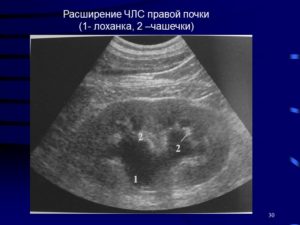

Первый отдел ЧЛС почек – это малые почечные чаши, которые имеют форму бокалов. Широким краем они охватывают сосочки пирамид, из которых выделяется моча. В здоровой почке их от 8 до 12.

И уже вглубь органа уходит ЧЛС почки. Система представляет собой небольшие бокалообразные чашки. В норме их количество в здоровом органе варьируется от 8 до 12.

Малые чашки почек посредством перегородок соединяются в большие чаши. Их уже насчитывают 2-3 штуки. А уже большие чаши сливаются в единую полость, имеющую форму лоханки.